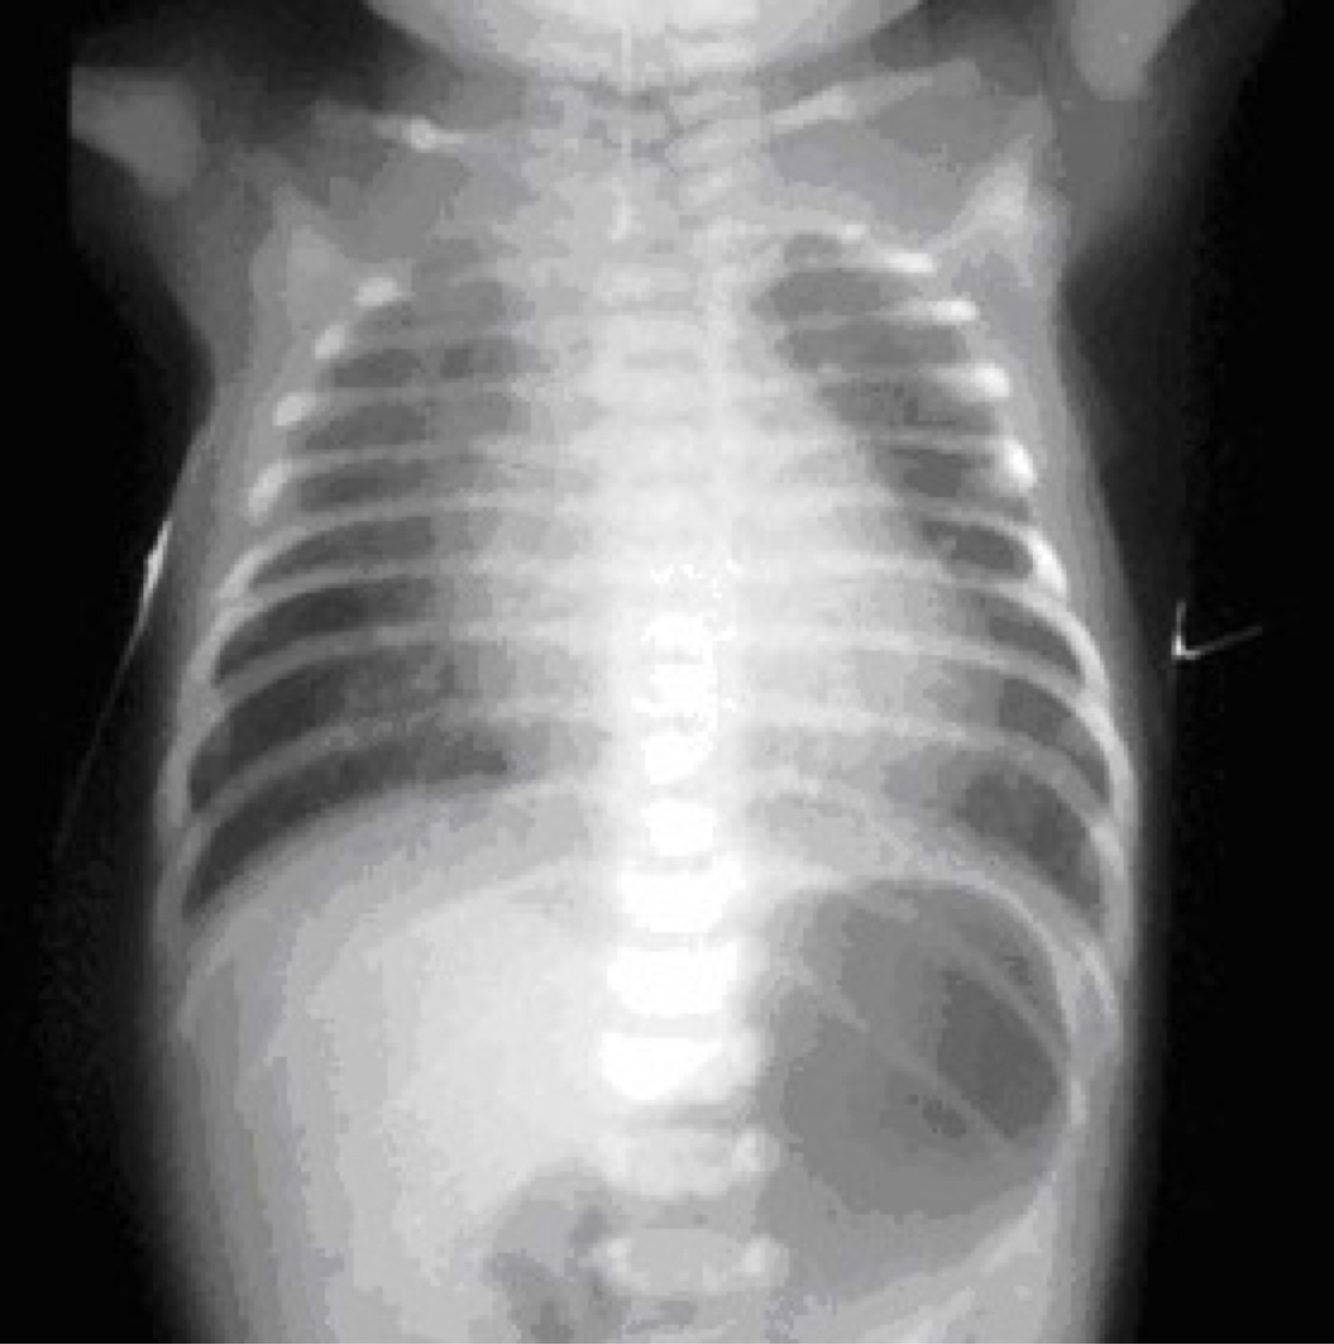

congenital diaphragmatic hernia